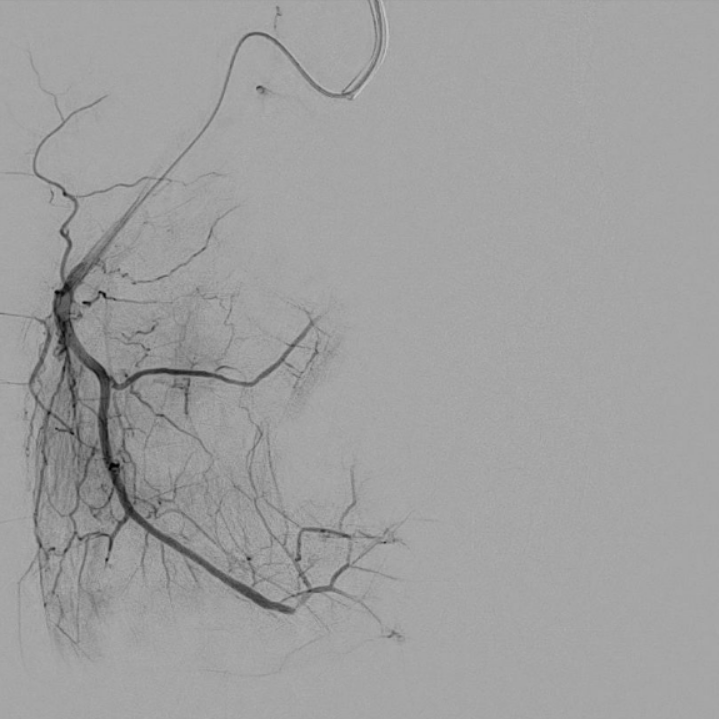

case of the day - 12.02.2026

Kniegelenk

Hier sehen Sie sehr eindrucksvoll die Behandlung des medialen Kniegelenksbereichs über die A. genicularis superior medialis.

Arteria genicularis superior medialis - vor Behandlung

Arteria genicularis superior medialis - nach Behandlung